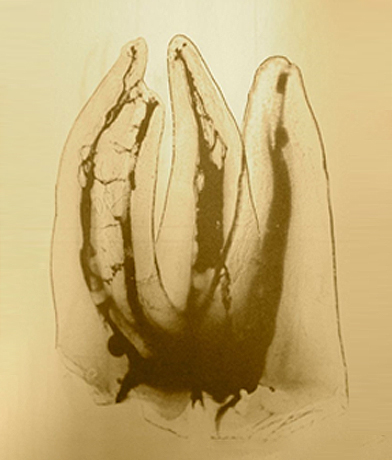

복잡한 신경관

충치로 염증이 생긴 치아

신경치료 후 치유된 치아